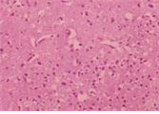

(바이러스) Western equine encephalitis virus

출처:CDC/ F. A. Murphy